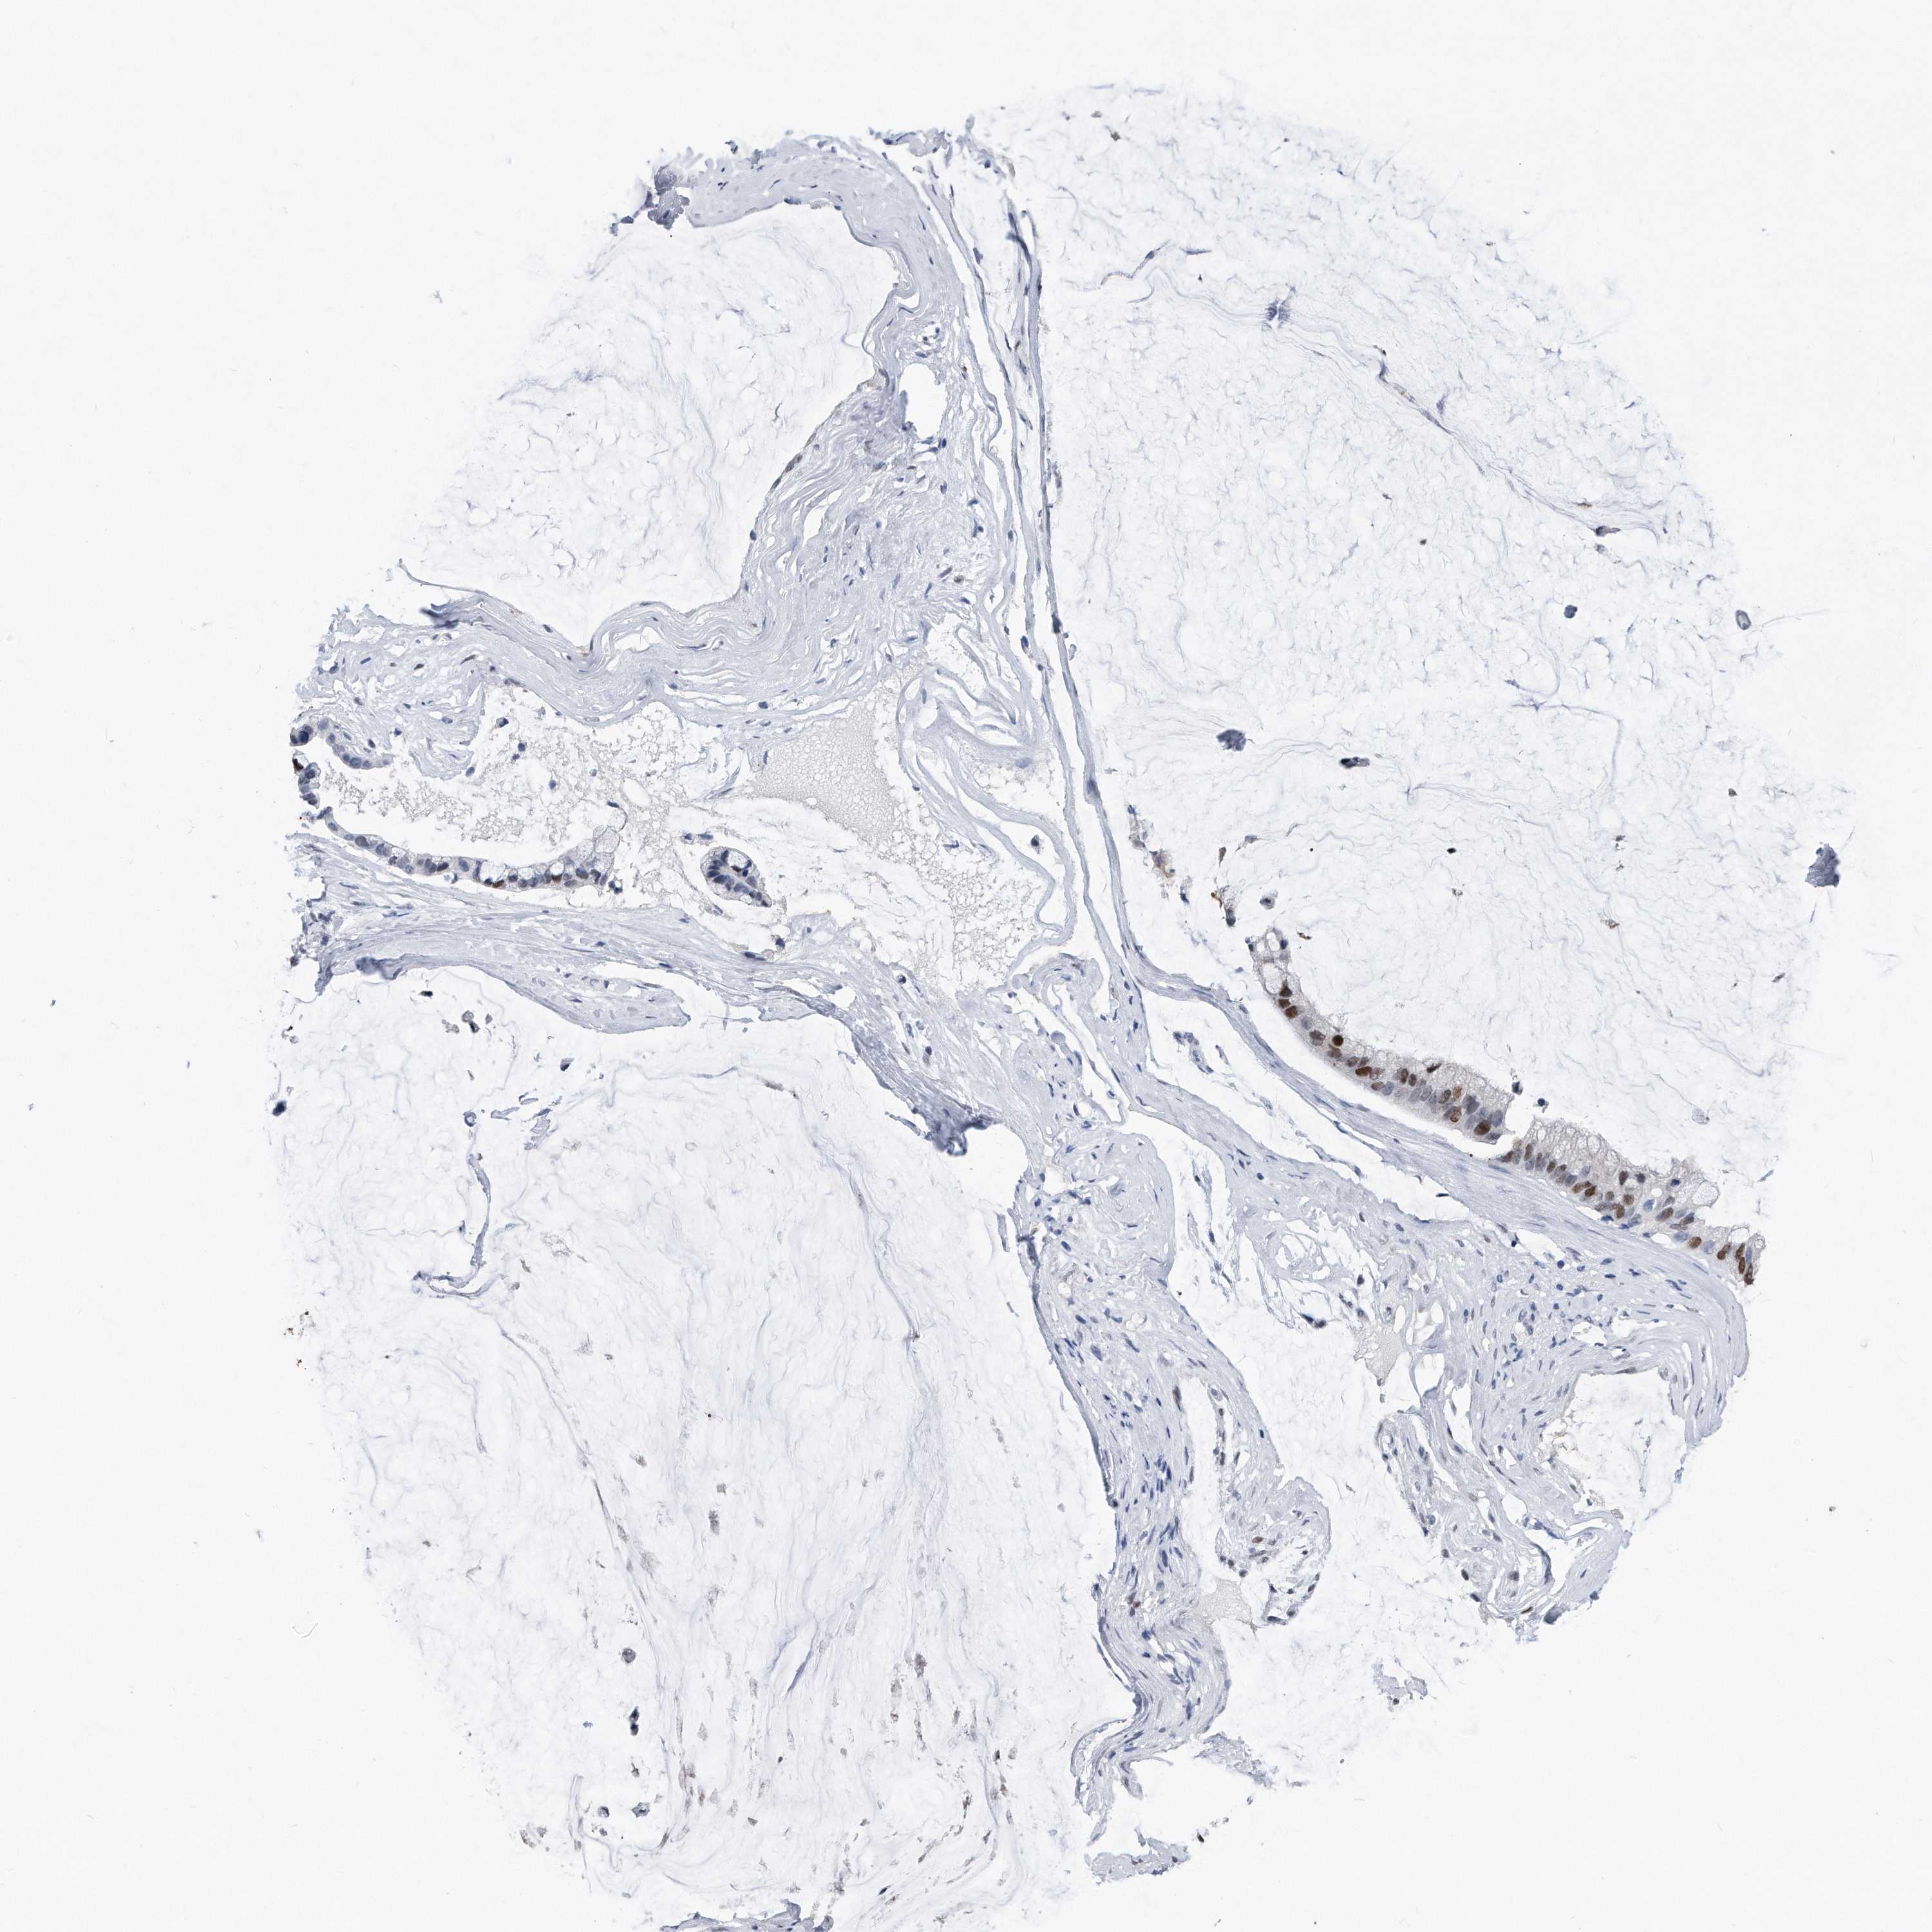

OVARIAN CANCER - Protein expressioni

A mouse-over function shows sample information and annotation data. Click on an image to view it in a full screen mode. Samples can be filtered based on level of antibody staining by selecting one or several of the following categories: high, medium, low and not detected. The assay and annotation is described here.

Note that samples used for immunohistochemistry by the Human Protein Atlas do not correspond to samples in the TCGA dataset.

Antibody stainingi

Antibody staining in the annotated cell types in the current human tissue is reported as not detected, low, medium, or high, based on conventional immunohistochemistry profiling in selected tissues. This score is based on the combination of the staining intensity and fraction of stained cells.

Each image is clickable and will lead to virtual microscopy that enables deeper exploration of all samples and also displays staining intensity scores, fraction scores and subcellular localization as well as patient and tissue information for each sample.

Cystadenocarcinoma, serous, NOS

Carcinoma, endometroid

Cystadenocarcinoma, mucinous, NOS

Carcinoma, NOS